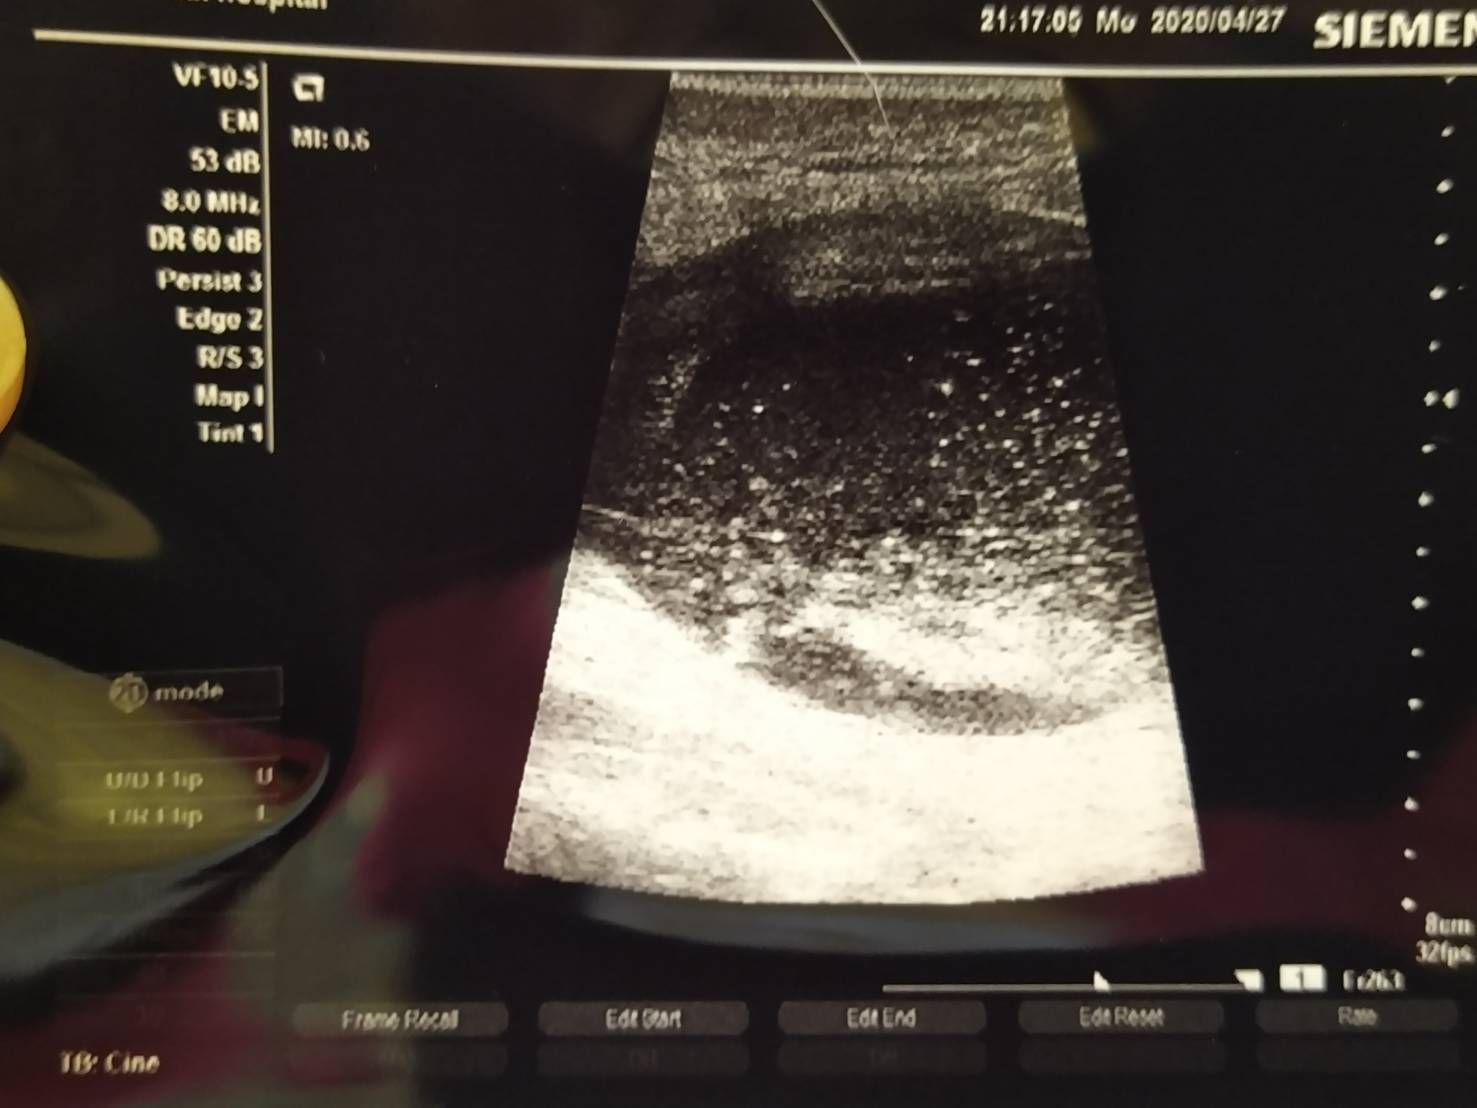

醫生說膀胱很硬,照了超音波,發現膀胱內都是結晶,尿道腫漲好幾倍,無法排尿

照超音波顯示膀胱內的結晶還有一半尚未排出,還有有些血尿